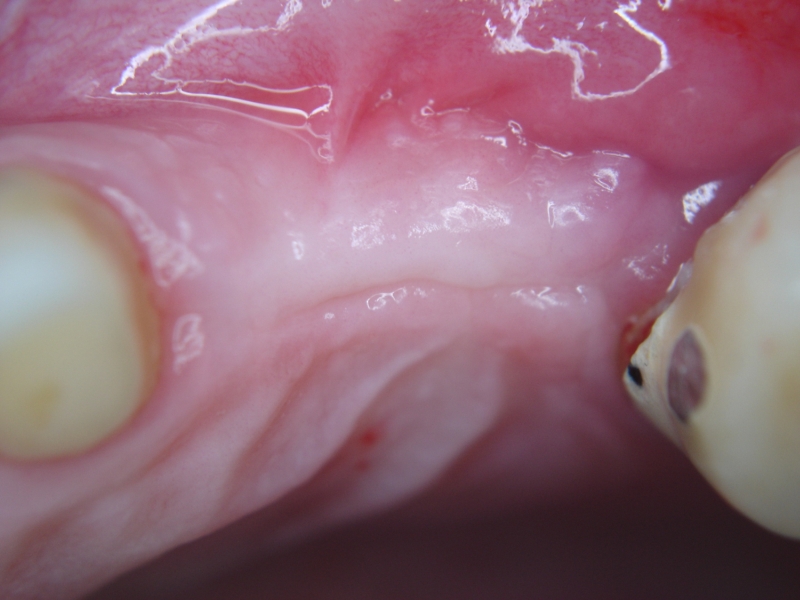

Initial situation: missing teeth #11 & 12 and badly broken #21 root